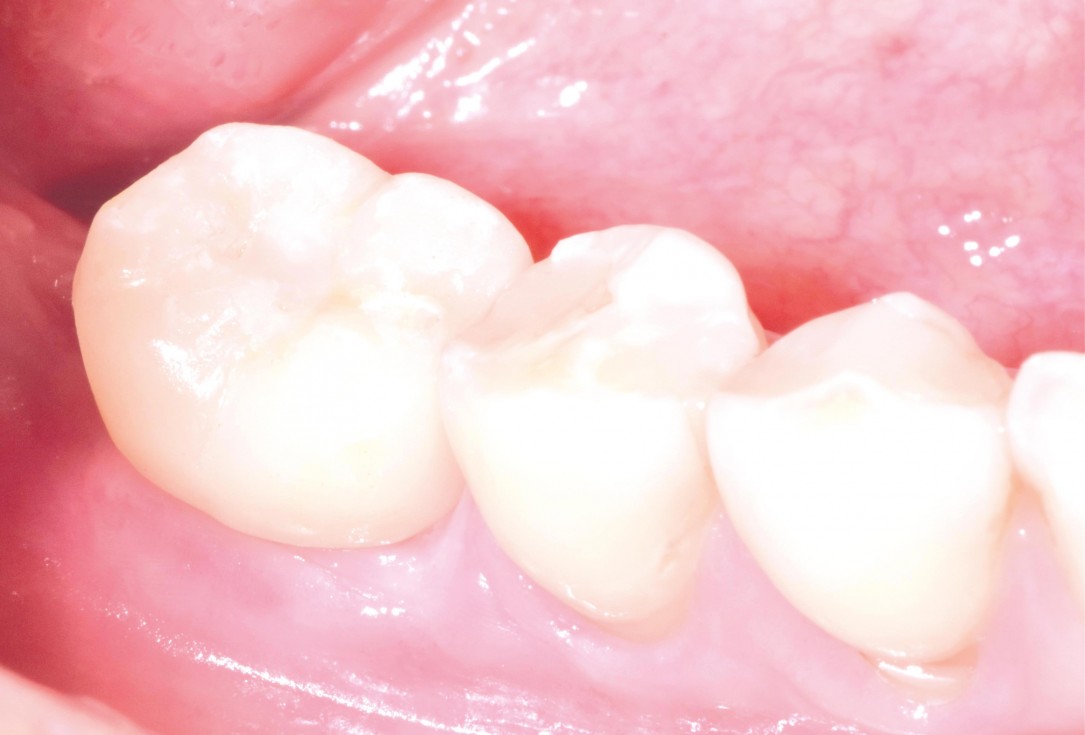

botiss maxgraft® bonebuilder aesthetic reconstruction - Clinical case